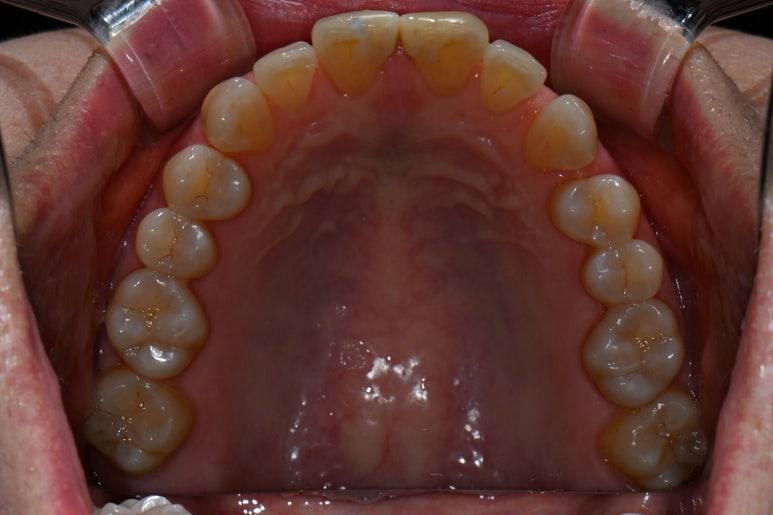

씹는 면에서 보시면 더욱 문제점이 잘 보입니다.

앞니 사이에 공간도 많으시고... 기존의 레진은 하염없이 두껍게만 붙여나가고 있는 수순이고..

앞니 벌어짐 + 레진 변색은 정말로 라미네이트 치료를 받기에 가장 적합한 경우라고 생각합니다.

그리고 하나 더 ! 이 분의 경우 아래 앞니에도 치아 사이 공간이 있어 많이 벌어짐이 있었는데요,

옛날부터 어르신들이 치아가 벌어져 있으면 복이 새어나간다고 하시잖아요~ 레진으로 양 옆에 붙여서 메꿔주는 것도 방법이지만, 얇은 세라믹을 붙여서 앞으로 변색 없이 완벽한 모양과 색상으로 유지해나가실 수 있을겁니다.

아래 앞니도 교합면에서 보면 생각보다 치아 사이 벌어짐이 많이 있으신 것을 보실 수 있을겁니다.